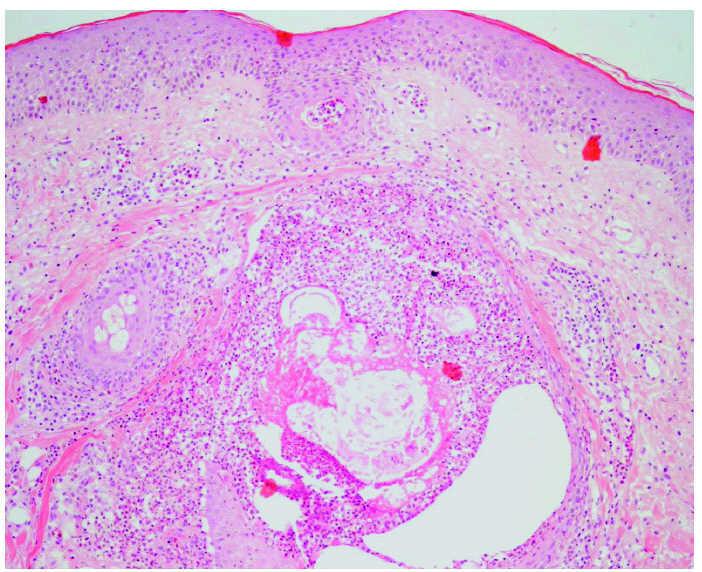

Histología

El patrón histológico se caracteriza por una florida foliculitis supurativa neutrofílica superficial 4,56,60,69,70,72 (fig. 5). Existe un denso infiltrado neutrofílico monomorfo predominantemente alrededor del infundíbulo 15,51,54,56,65. En ocasiones hay tendencia a formar microabscesos 72 y células gigantes multinucleadas 67, además puede existir un infiltrado linfohistiocitario acompañante 65,66. La glándula sebácea, a diferencia de lo que cabría pensar por la distribución de las lesiones, no se encuentra afectada 4,15,72,79. La capa córnea se encuentra adelgazada y pierde su aspecto en cesta de mimbre 4,15,48,79,80, aunque algún autor ha encontrado hiperqueratosis ortoqueratósica 67. Con gefitinib existe un mayor número de células apoptóticas en la epidermis y cierta degeneración de la capa basal 4,48,49,67.

Fig. 5.--Foliculitis y perifoliculitis aguda. (Hematoxilina-eosina, ×40.)

Un estudio realizado en pacientes sometidos a tratamiento con gefitinib 4 y otro con 10 pacientes sometidos a cetuximab 60 fueron sometidos a biopsias previas y durante el tratamiento, encontrando un estrato córneo adelgazado que perdía su aspecto en cesta de mimbre y estaba más compacto y eosinofílico, con ocasionales focos de paraqueratosis. En algunas biopsias se observaba un infiltrado mononuclear focal con degeneración focal de la capa basal de la epidermis y queratinocitos necróticos similar a la descrita en las reacciones liquenoides. Los cambios más iniciales eran un infiltrado linfocitario T (CD45RO) alrededor del infundíbulo folicular 60. En algunas biopsias se observaban tapones foliculares sobre unos infundíbulos dilatados similares a comedones 4,60. En otros pacientes se ha observado una acantolisis focal asociada a un infiltrado neutrofílico disperso que afectaba la zona terminal del conducto sudoríparo 60, cuyo significado no está aclarado 43. No se observaban alteraciones de los vasos sanguíneos, glándulas ecrinas ni sebáceas. Estos cambios son similares a los que presentan ratones que no expresan el EGFR (knock-out), si bien en los ratones además de verse un adelgazamiento de la capa córnea también se observa un adelgazamiento de toda la epidermis 9,10.

En estudios de inmunohistoquímica se ha encontrado un aumento importante en la expresión de p27Kip1 que es una proteína que inhibe la proliferación y produce una detención celular en la fase G1, este efecto que también se produce en las células tumorales es la base de su efecto antineoplásico 4,60,76,79. También una inhibición de la proteincinasa mitógena activada (activated mitogen-activated protein kinase) una cinasa que promueve la proliferación celular, un aumento de la tasa de apoptosis 4, así como una disminución de la expresión del EGFR y del marcador de proliferación Ki67 4.